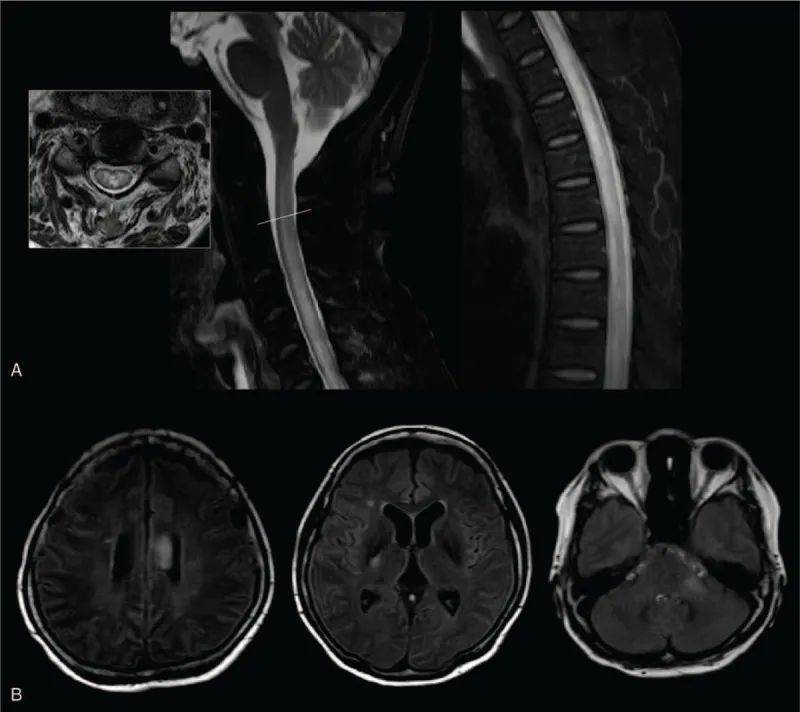

视神经脊髓炎谱系障碍(NMOSD)是一种自身免疫性神经疾病,全球发病率为估计为1.82/10万人。这种疾病的特点是视神经、脊髓、脑干和大脑的炎症性病变,可能会导致严重的运动和感觉障碍、膀胱功能障碍、视力丧失、疼痛和其他衰弱症状。这种疾病恢复是可变的,炎症发作往往有可能会导致永久性残疾。